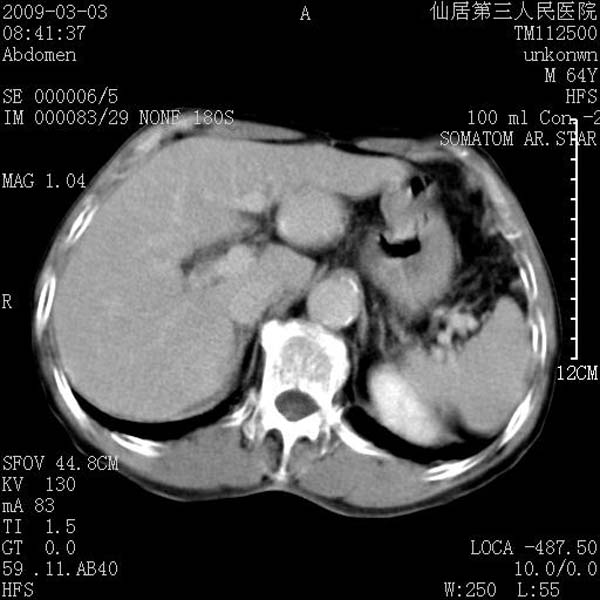

标题: CT18469:男性,64y,体检B超示肝脏低回声肿块,有胃溃疡手术 [打印本页]

标题: CT18469:男性,64y,体检B超示肝脏低回声肿块,有胃溃疡手术

患者,男性,64y,体检b超示肝脏低回声肿块,有胃溃疡手术史。

考虑----胃肠道间质瘤可能性大

从平扫及增强的特点来看,支持肝脏腺瘤并出血。

考虑胃间质瘤可能性大。

胃肠道间质瘤!

ct值呢?感觉没强化,象囊性。

考虑肝静脉韧带裂区良性占位性病变(囊肿?)。

考虑肝囊肿并出血可能性大.

考虑高密度囊肿可能性大